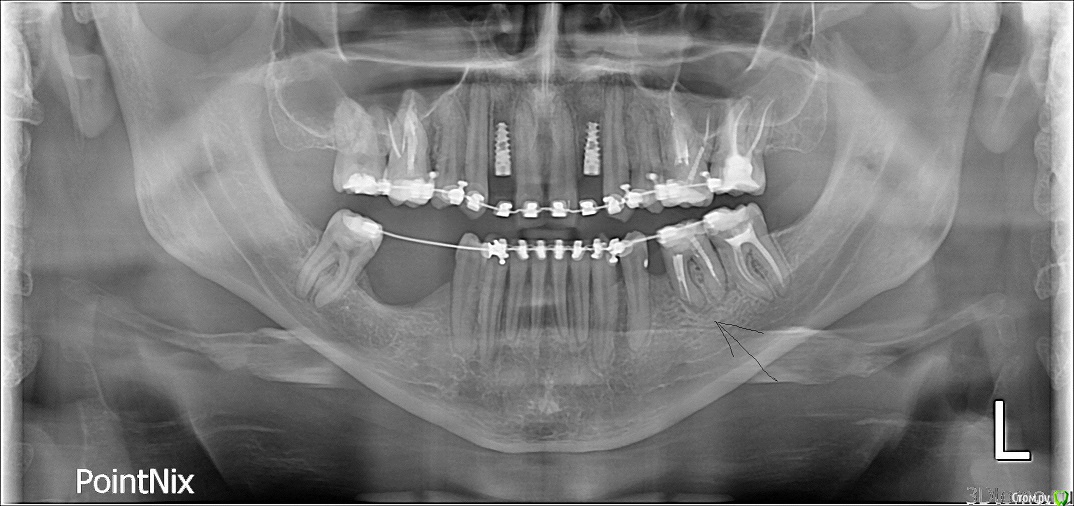

andr1241 Опубликовано 4 декабря, 2015 Поделиться Опубликовано 4 декабря, 2015 После орт. лечения хочу ставить импланты. мне хирург предлагает вырвать зуб (на фото отметил) и поставить там 2 импланта. Вырвать хочет по причине того что мало место для 1-го импланта и на зубе киста. Я бы хотел чтобы поставил 1 имплант тонкий, и удалить кисту с верхушкой корня, чтобы сохранить зуб. Он говорит что удаление кисты и верхушки зуба можно делать если зуб однокоренной, на многокоренных очень частые рецидивы. Если кто специалист посоветуйте следует ли соглашаться на удаление или нет? Ссылка на комментарий